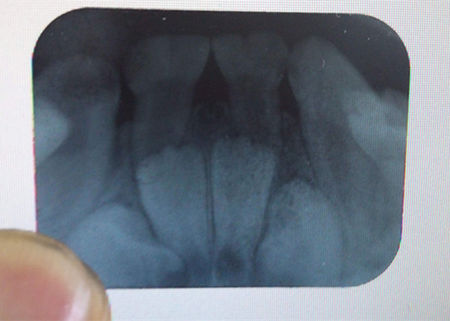

如圖躲在暗處的危險(xiǎn),如果單用肉眼是很難察覺(jué)的,通過(guò)X光片能發(fā)現(xiàn)牙齒鄰面區(qū)有多處小暗點(diǎn)(比較淺的蛀牙),而且你也沒(méi)什么感覺(jué),頂多吃飯塞牙,敏感些而已。